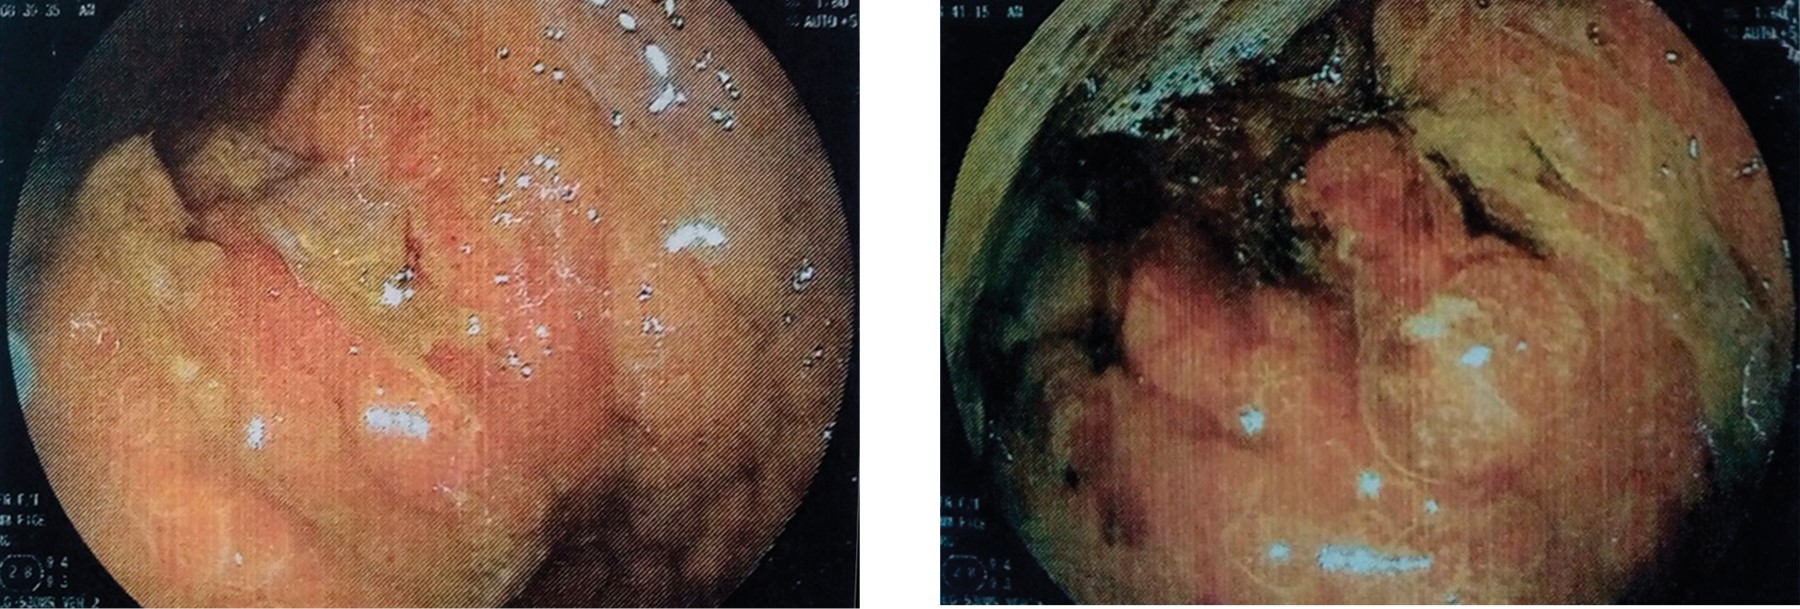

A 68 year-old male patient with history of diabetes mellitus, smoking, and chronic alcoholism for more than 20 years. He denied surgical history. The patient presented with intermittent abdominal distension, dyspepsia, progressive dysphagia from solids to liquids. He denied weight loss or data of gastrointestinal tract bleeding. A CT scan with intravenous contrast reported a right renal tumor of 7 × 6 × 4 cm with rounded edges, well defined, and a heterogeneous hypodense center related to cystic or necrotic degeneration (Figure 1). After intravenous contrast, a "claw sign" was present, with enhancement at 20 HU and a delayed triphasic phase enhancement of 10 HU. Also, a distended stomach with thickening of the antral and pyloric mucosa of 1.7 cm was found, with no hepatic or distant metastases. Panendoscopy showed infiltrating gastric neoplasia (Borrmann II adenocarcinoma) (Figure 2). The histopathological result of the gastric biopsy reported a poorly differentiated diffuse infiltrating adenocarcinoma with signet ring cells. The CA 19-9 marker value was 126 U/ml.

Figure 2